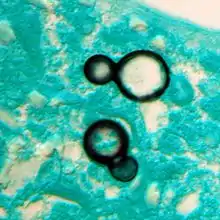

Once suspected, the diagnosis of blastomycosis can usually be confirmed by demonstration of the characteristic broad based budding organisms in sputum or tissues by KOH prep, cytology, or histology.[27] Tissue biopsy of skin or other organs may be required in order to diagnose extra-pulmonary disease. Blastomycosis is histologically associated with granulomatous nodules.

Large yeast-like fungi seen within giant cells at arrows. Large yeast-like fungi seen within giant cells at arrows. Budding yeasts in cytoplasm of giant cells at arrows. Broad-based budding and double contoured cell wall seen in the giant cell in the center is characteristic of Blastomyces dermatitidis.